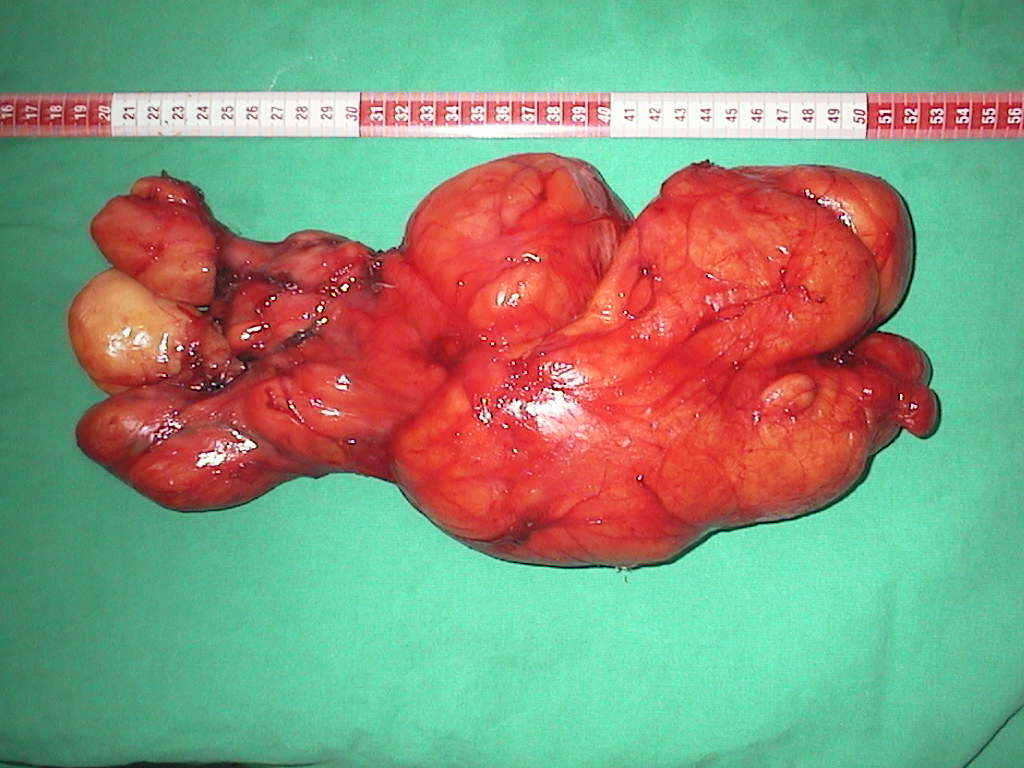

Surgical Specimen - entire.

Piesa operatorie - întreagă.